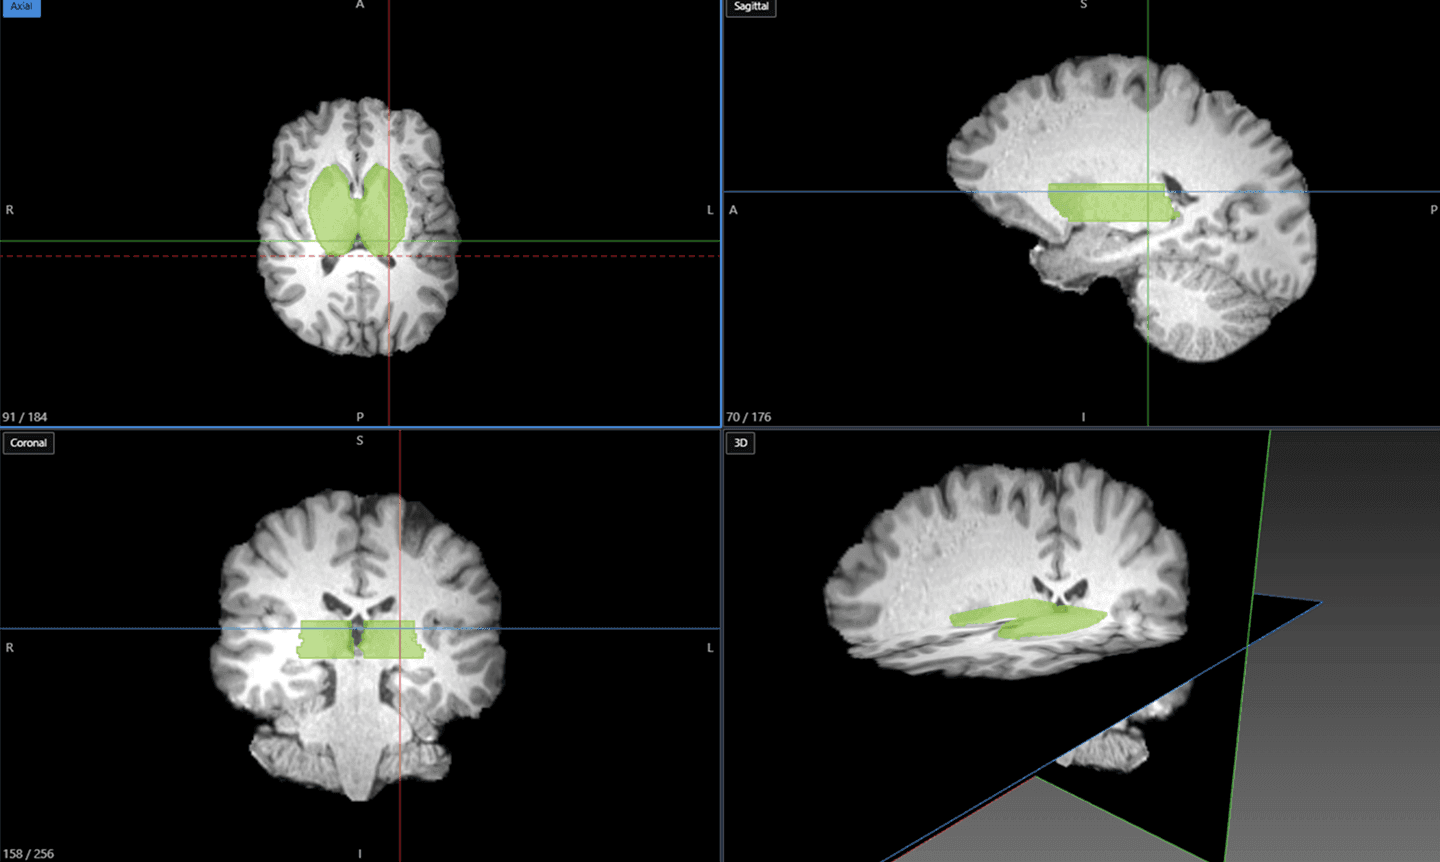

층적 어노테이션을 지원하여 자동 병변 감지, 장기 및 구조 세분화 등 고급 기능을 구현합니다.

뼈와 세포 형태를 사전에 식별하는 의료 특화 모델을 기반으로, 계층적 데이터 라벨링을 지원하고 자동 병변 감지와 같은 고급 기능을 구현합니다.